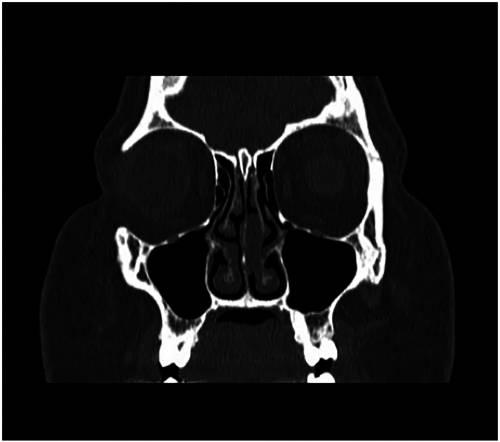

一名37岁的成年女性患者,有5年间歇性双侧鼻塞和面部疼痛及肿胀病史。否认有嗅觉缺失和鼻出血。既往有严重的II型糖尿病和高血压病史。之前没有做过鼻腔手术,也没有鼻腔外伤史。检查发现鼻中隔偏曲,左鼻中鼻道内见一新生物,阻塞左侧中鼻道。CT检查结果显示粘膜息肉样外观,部分阻塞左鼻道,鼻腔粘膜增厚,引流无阻塞(见图1)。

图1 CT检查显示粘膜息肉样编,部分阻塞左鼻道,粘膜增厚,引流路径无阻塞